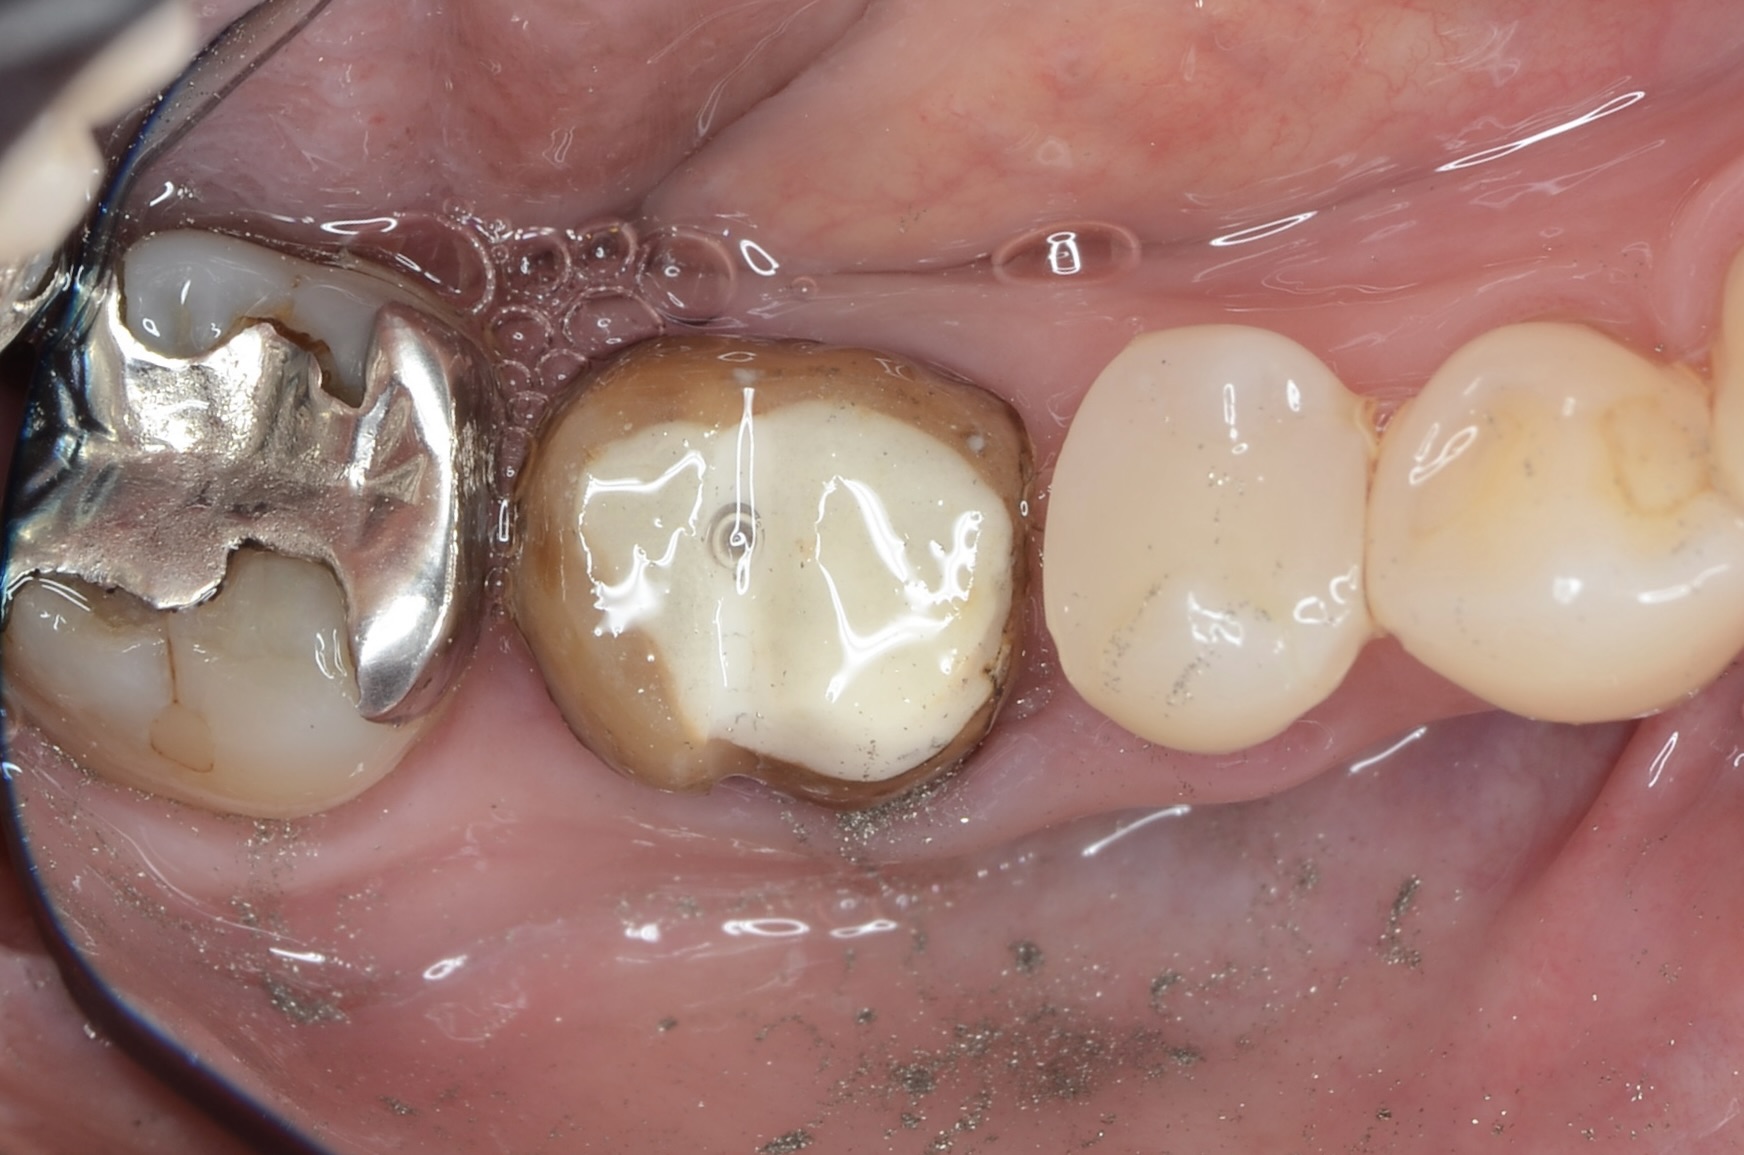

クラウン除去

-

レジンコア除去後